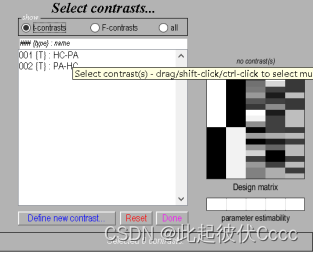

3.输入对比矩阵名称如HC-PA,输入对比矩阵,1 -1表示第一组减去第二组,点击OK,点击Done,即添加了一组,这里添加两组,分别为HC-PA与PA-HC,如下图所示:

4.点击Done,之后按下图进行选择